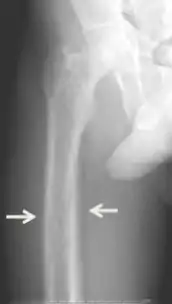

Brown tumors in the pelvis and a hip fracture.[13]